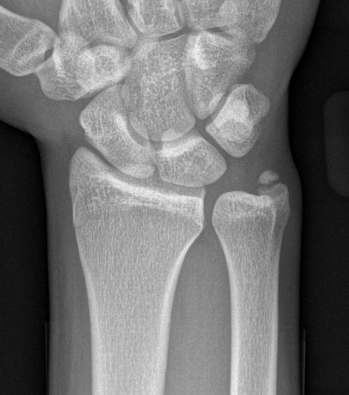

DRUJ instability after distal radius fracture

1. Ulna styloid fracture

2. No ulna styloid fracture / TFCC injury

Ulna styloid fractures occur in half of all distal radius fractures

Classification ulna styloid fractures

| Type 1: Tip | Type 2: Base | Type 3: Proximal to styloid |